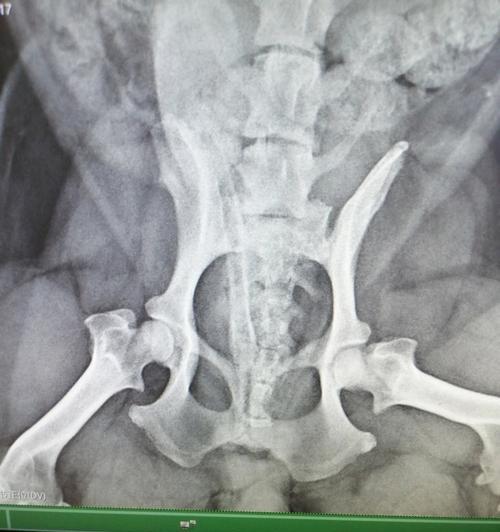

狗狗腿髋坏死的成因与治疗全解析 腿髋坏死是狗狗常见且严重的骨骼疾病,主要由血液供应不足引起。了解其成因和预防措施,有助于降低患病风险。治疗方式包括非手术和手术,配合兽医进行科学护理是关键。主人的关爱与耐心对狗狗康复同样重要,及时诊断和治疗可有效提升生活质量。 养护知识 2026-02-22 05:46 浏览:560